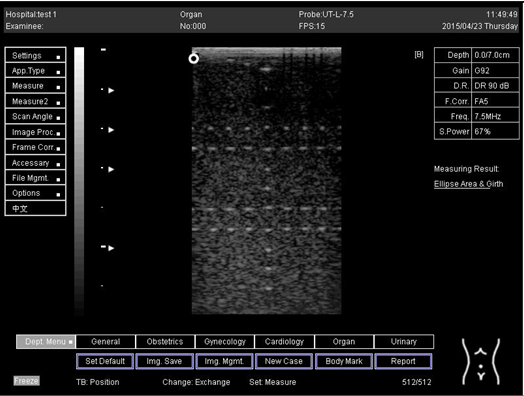

Lateral resolution

Biomimetics 07 00130 i002

D1 = 5.0

D2 = 4.0

D3 = 3.0

D4 = 2.2